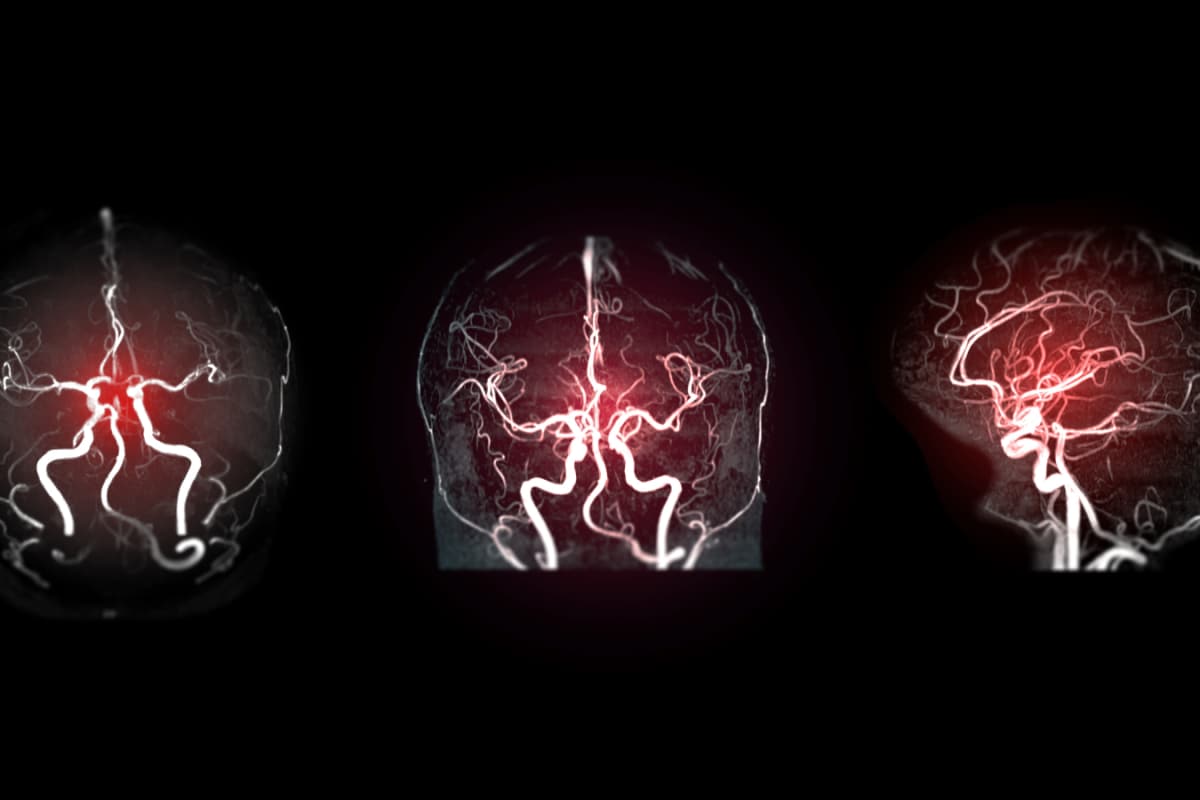

According to ICMR study, which examined 34,792 stroke cases registered across 30 hospitals between January 2020 and December 2022, 1 in 7 stroke patients.